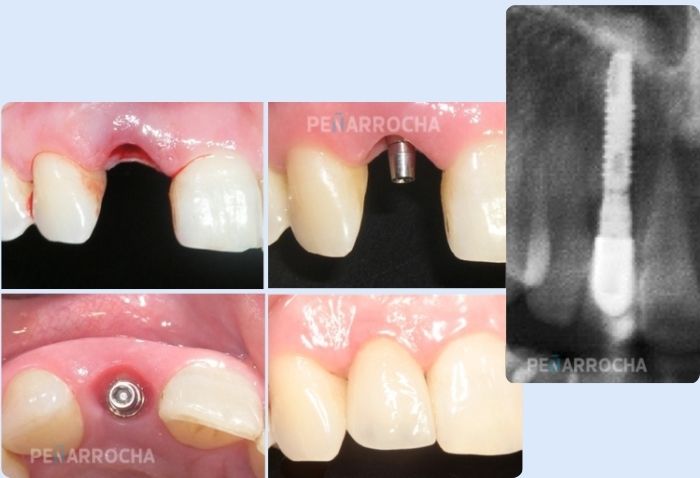

La carga inmediata puede ser utilizada para reemplazar dientes unitarios, segmentos edéntulos parciales o arcadas completas.

3 - Prótesis fija provisional

Tras la colocación de los implantes, se fija una prótesis provisional que permite recuperar la funcionalidad y la estética de forma inmediata. Esta prótesis se adapta a los implantes y permite masticar alimentos blandos durante el período de cicatrización.

Una vez completada la osteointegración, se reemplaza la prótesis provisional por una definitiva diseñada a medida, garantizando una estética natural y una funcionalidad completa.